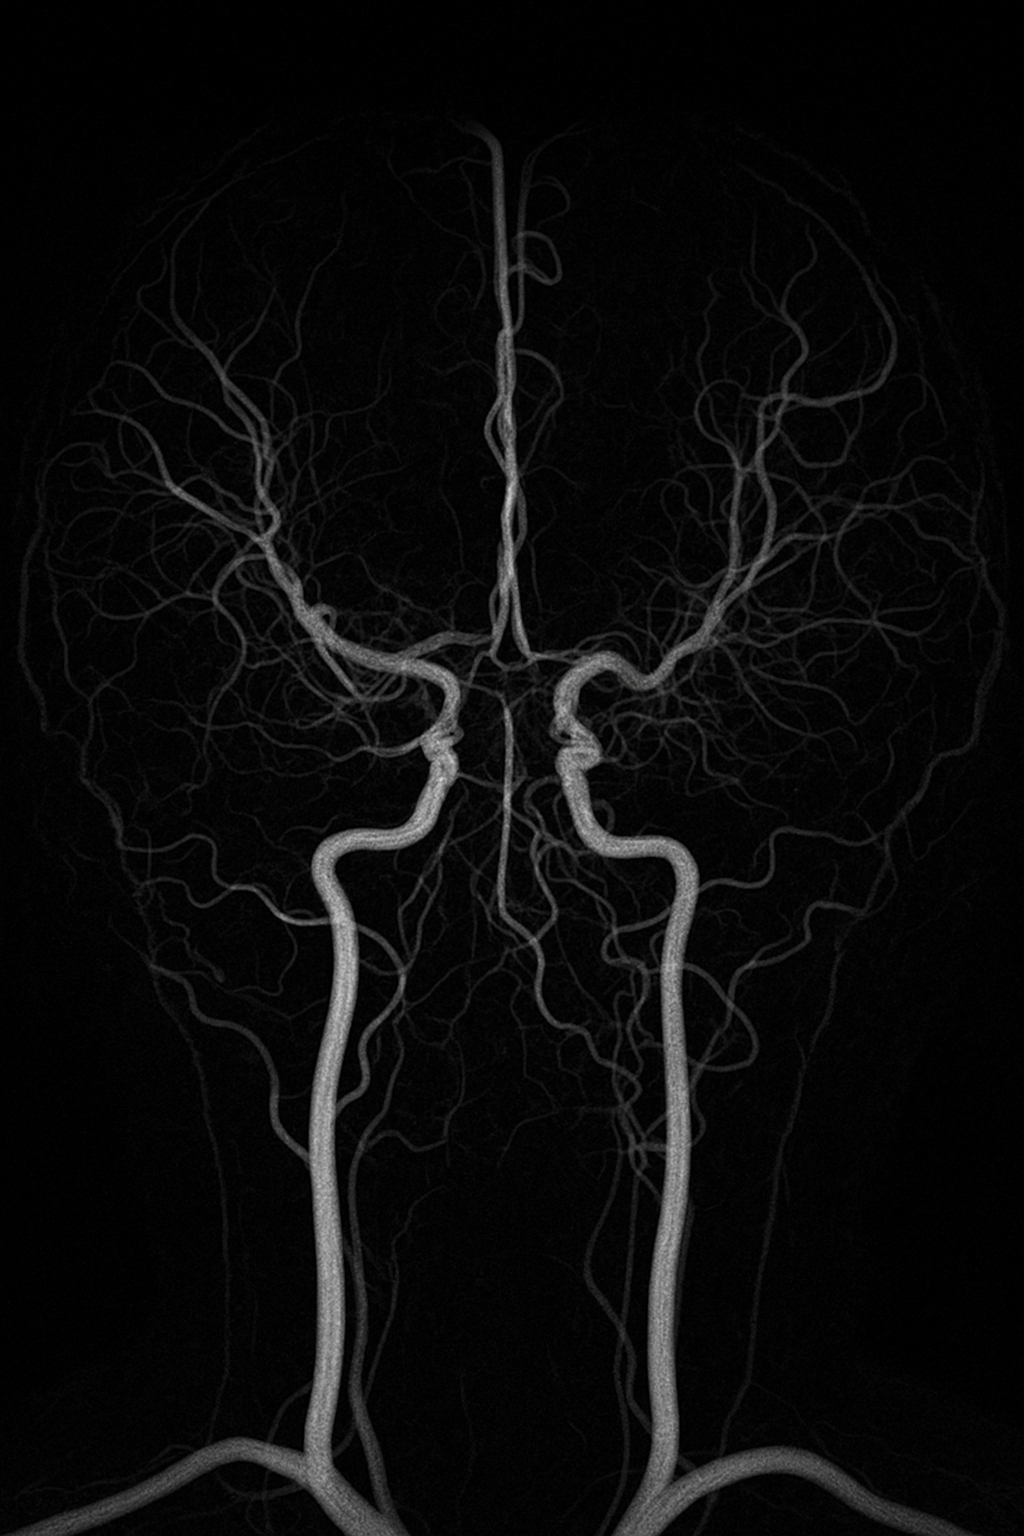

모야모야병(Moyamoya disease)은 뇌의 주요 혈관이 서서히 좁아지고,

이로 인해 뇌로 가는 혈류가 줄어드는 희귀한 진행성 뇌혈관 질환입니다.

좁아진 혈관 주변에는 작은 모세혈관들이 새롭게 자라는데,

이 모습이 일본어로 '모야모야'(연기가 피어오르는 것처럼 보임)처럼 보여서 붙여진 이름입니다.

- 뇌 MRI 및 MRA: 뇌혈관의 협착 및 모세혈관 확인

- 뇌혈관조영술: 혈관 구조를 가장 정밀하게 확인